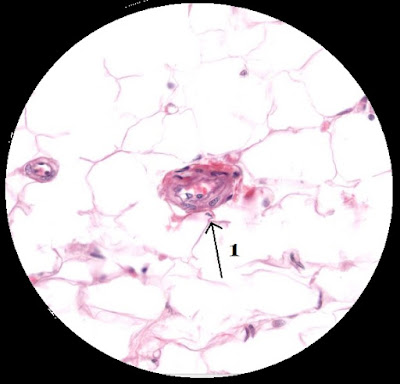

ARTERIOLA

Tomado de Histology guide1. Arteriola: Arterias de pequeño calibre con función de regular el flujo a los capilares por contracción de las células del músculo liso.

1. Membrana elástica interna: Capa elástica que ayuda a proporcionar resistencia al estiramiento del vaso sanguíneo.

2. Túnica media: Capa de células musculares lisas con fibras elásticas que dan elasticidad y resistencia a los vasos sanguíneos.

3. Células endoteliales: Células planas con múltiples funciones como la regulación la angiogénesis, el remodelado vascular, mantenimiento de la MEC y participación en el metabolismo de lipoproteínas.

4. Células musculares lisas: Recubren los vasos sanguíneos y son responsables de la contracción.